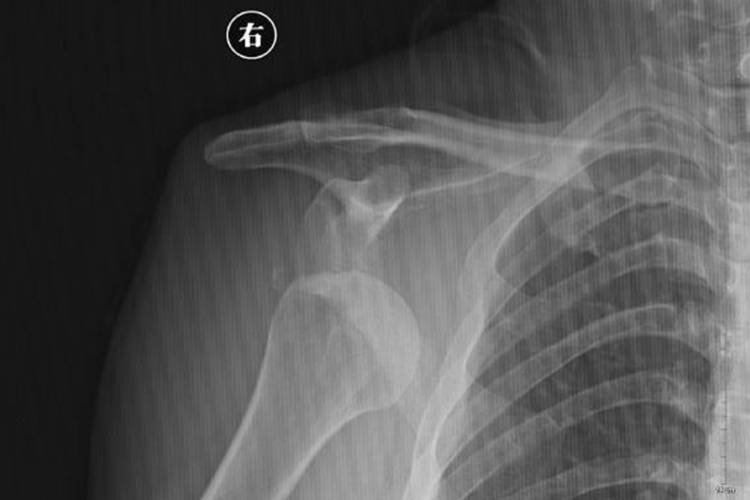

肩关节脱位主要由于暴力导致,可出现肩部疼痛、肿胀、活动障碍等症状,借助X线可了解肱骨头脱位类型,一般分为前脱位和后脱位。

肩关节脱位患者常有上肢外展外旋或后伸着地受伤史,可出现肩部疼痛、肿胀、活动障碍,以及有以健手托住病侧前臂、头向病侧倾斜的特殊姿势。通常X线检查可确诊,常见肱骨头前脱位,偶见肱骨头后脱位。肱骨头前脱位可见X线片骨影向下移位,位于肩胛盂下方,称为盂下脱位,此外还可向上移位,位于喙突下方或锁骨下方等位置。肱骨头后脱位一般表现为肱骨头在肩胛盂后方。